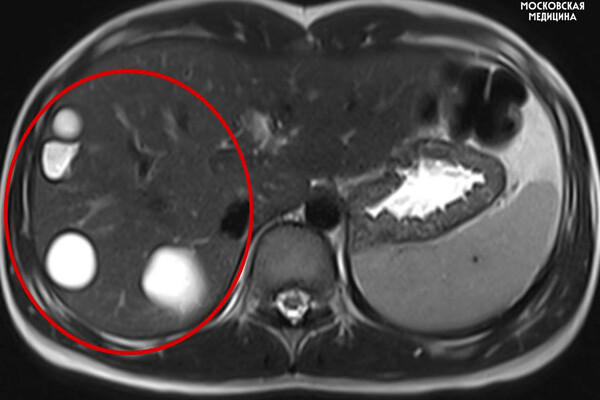

Врачи больницы имени Сперанского спасли 14-летнюю девочку с множеством паразитарных кист в печени. Об этом сообщили в пресс-службе столичного департамента здравоохранения.

Кисты медики обнаружили случайно во время планового обследования. После этого ребенка направили на операцию.

Во время вмешательства специалисты удалили пять кист с использованием лапароскопии. Через пять дней после операции пациентку выписали домой.